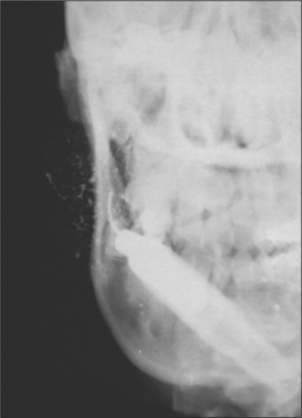

sialography reveals the progressive damage from punctate sialectasis to total parenchymal destruction leaving no more than a grossly dilated duct (Fig. 14.12)

image

Fig. 14.12 Parotid sialogram showing gross destruction of parotid parenchyma in a patient with advanced Sjögren’s syndrome.